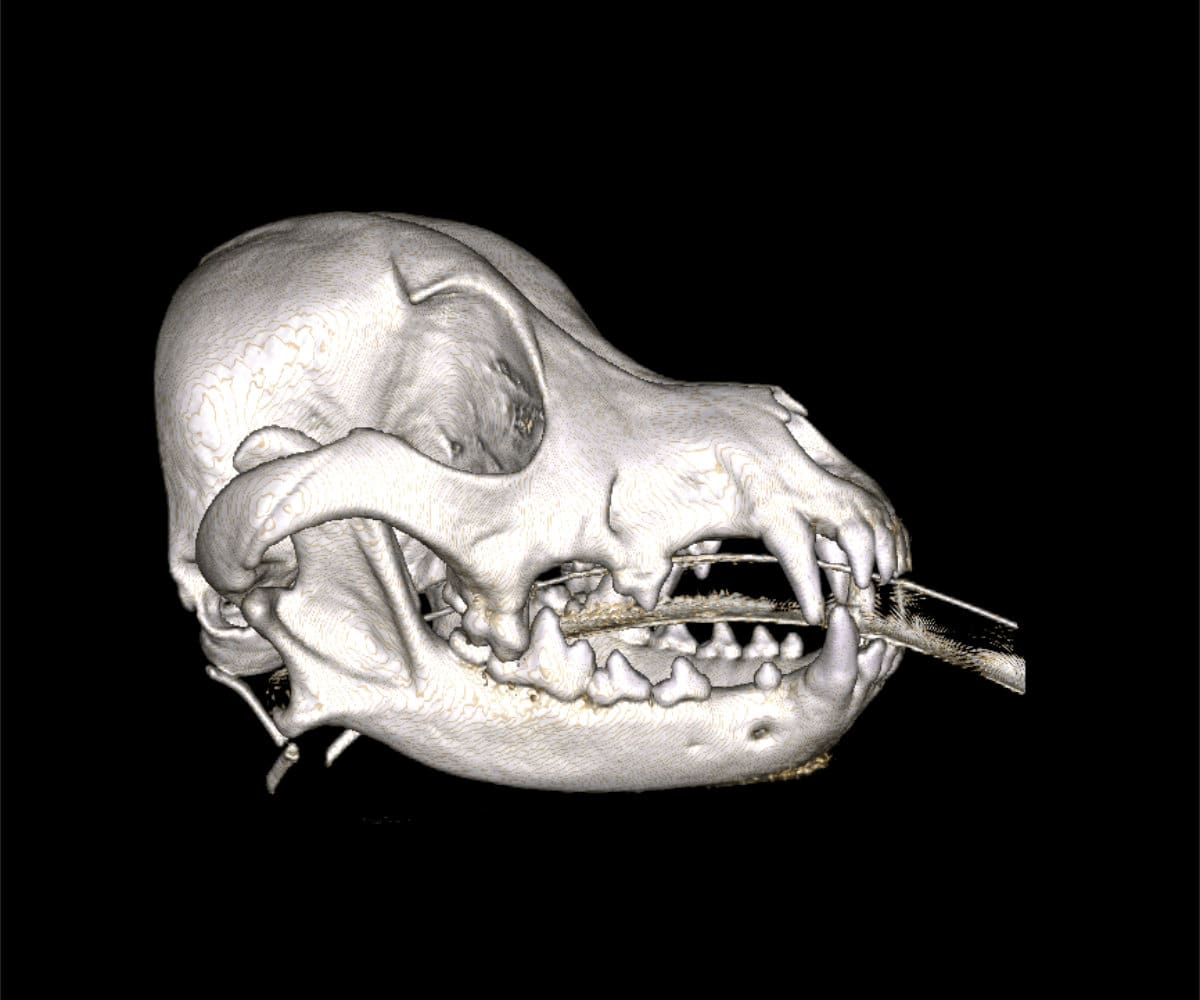

In addressing these limitations, CBCT emerges as a pivotal advancement. Conducting a CBCT scan on our patients is characterized by minimal time and effort, effectively reducing anesthesia duration. Moreover, this technology facilitates the generation of a comprehensive 3D reconstruction of the teeth and skull, surpassing the constraints of traditional radiographs. This innovative approach empowers our veterinary professionals to identify oral pathologies that may have been missed on traditional radiographs.

The advantages extend beyond diagnosis, as CBCT enables intricate 3D reconstructions of the skull, providing invaluable support to our doctors in the meticulous planning process for facial plating procedures.

Our CBCT VetCAT unit is easily rolled up to our treatment table and takes only 40 seconds to complete a scan. It has proven to be invaluable in the diagnosis and treatment planning for pets with periodontal, endodontic and cancerous disease conditions. It is also indispensable in the evaluating our trauma cases with jaw fractures.